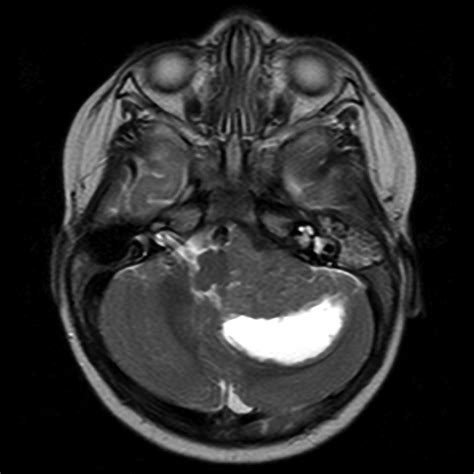

Because these tumors are highly malignant and classified as Grade IV under the World Health Organization (WHO) classification of central nervous system tumors, they grow quickly and can invade surrounding healthy brain tissue. Unlike many other brain tumors, an Atypical Teratoid Tumor can manifest in various locations within the brain or spinal cord, complicating the surgical approach and overall prognosis.

Diagnosis typically begins with advanced neuroimaging, such as MRI scans with and without contrast, to visualize the tumor's size and location. However, imaging alone is rarely sufficient. A definitive diagnosis is achieved through a surgical biopsy or total resection, followed by a rigorous pathological examination. Pathologists look for the loss of INI1 protein expression in the tumor cells, which serves as a molecular hallmark for an Atypical Teratoid Tumor.

• Atypical Teratoid Rhabdoid Tumor MRI